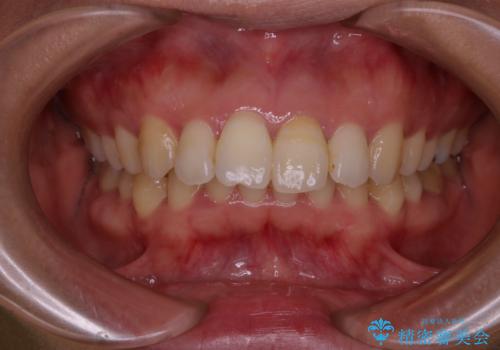

- 前歯の色が気になるとのことでご相談にいらした患者様です。診断の結果、前歯は2本とも失活していたために精密根管治療から治療を開始しました。根管治療後にウォーキングブリーチを行うことで歯の色をトーンアップさせました。患者様より周囲の歯も全体的に白くしたいとのご希望があったため、オフィスホワイトニングも併せて行いました。

ウォーキングブリーチ法とは歯の中に薬剤を入れて内側からホワイトニングを行う方法であるため、根管治療がされている歯のみ適応となります。生活歯(神経が生きている歯)に対してはオフィスホワイトニングやホームホワイトニングが有効です。